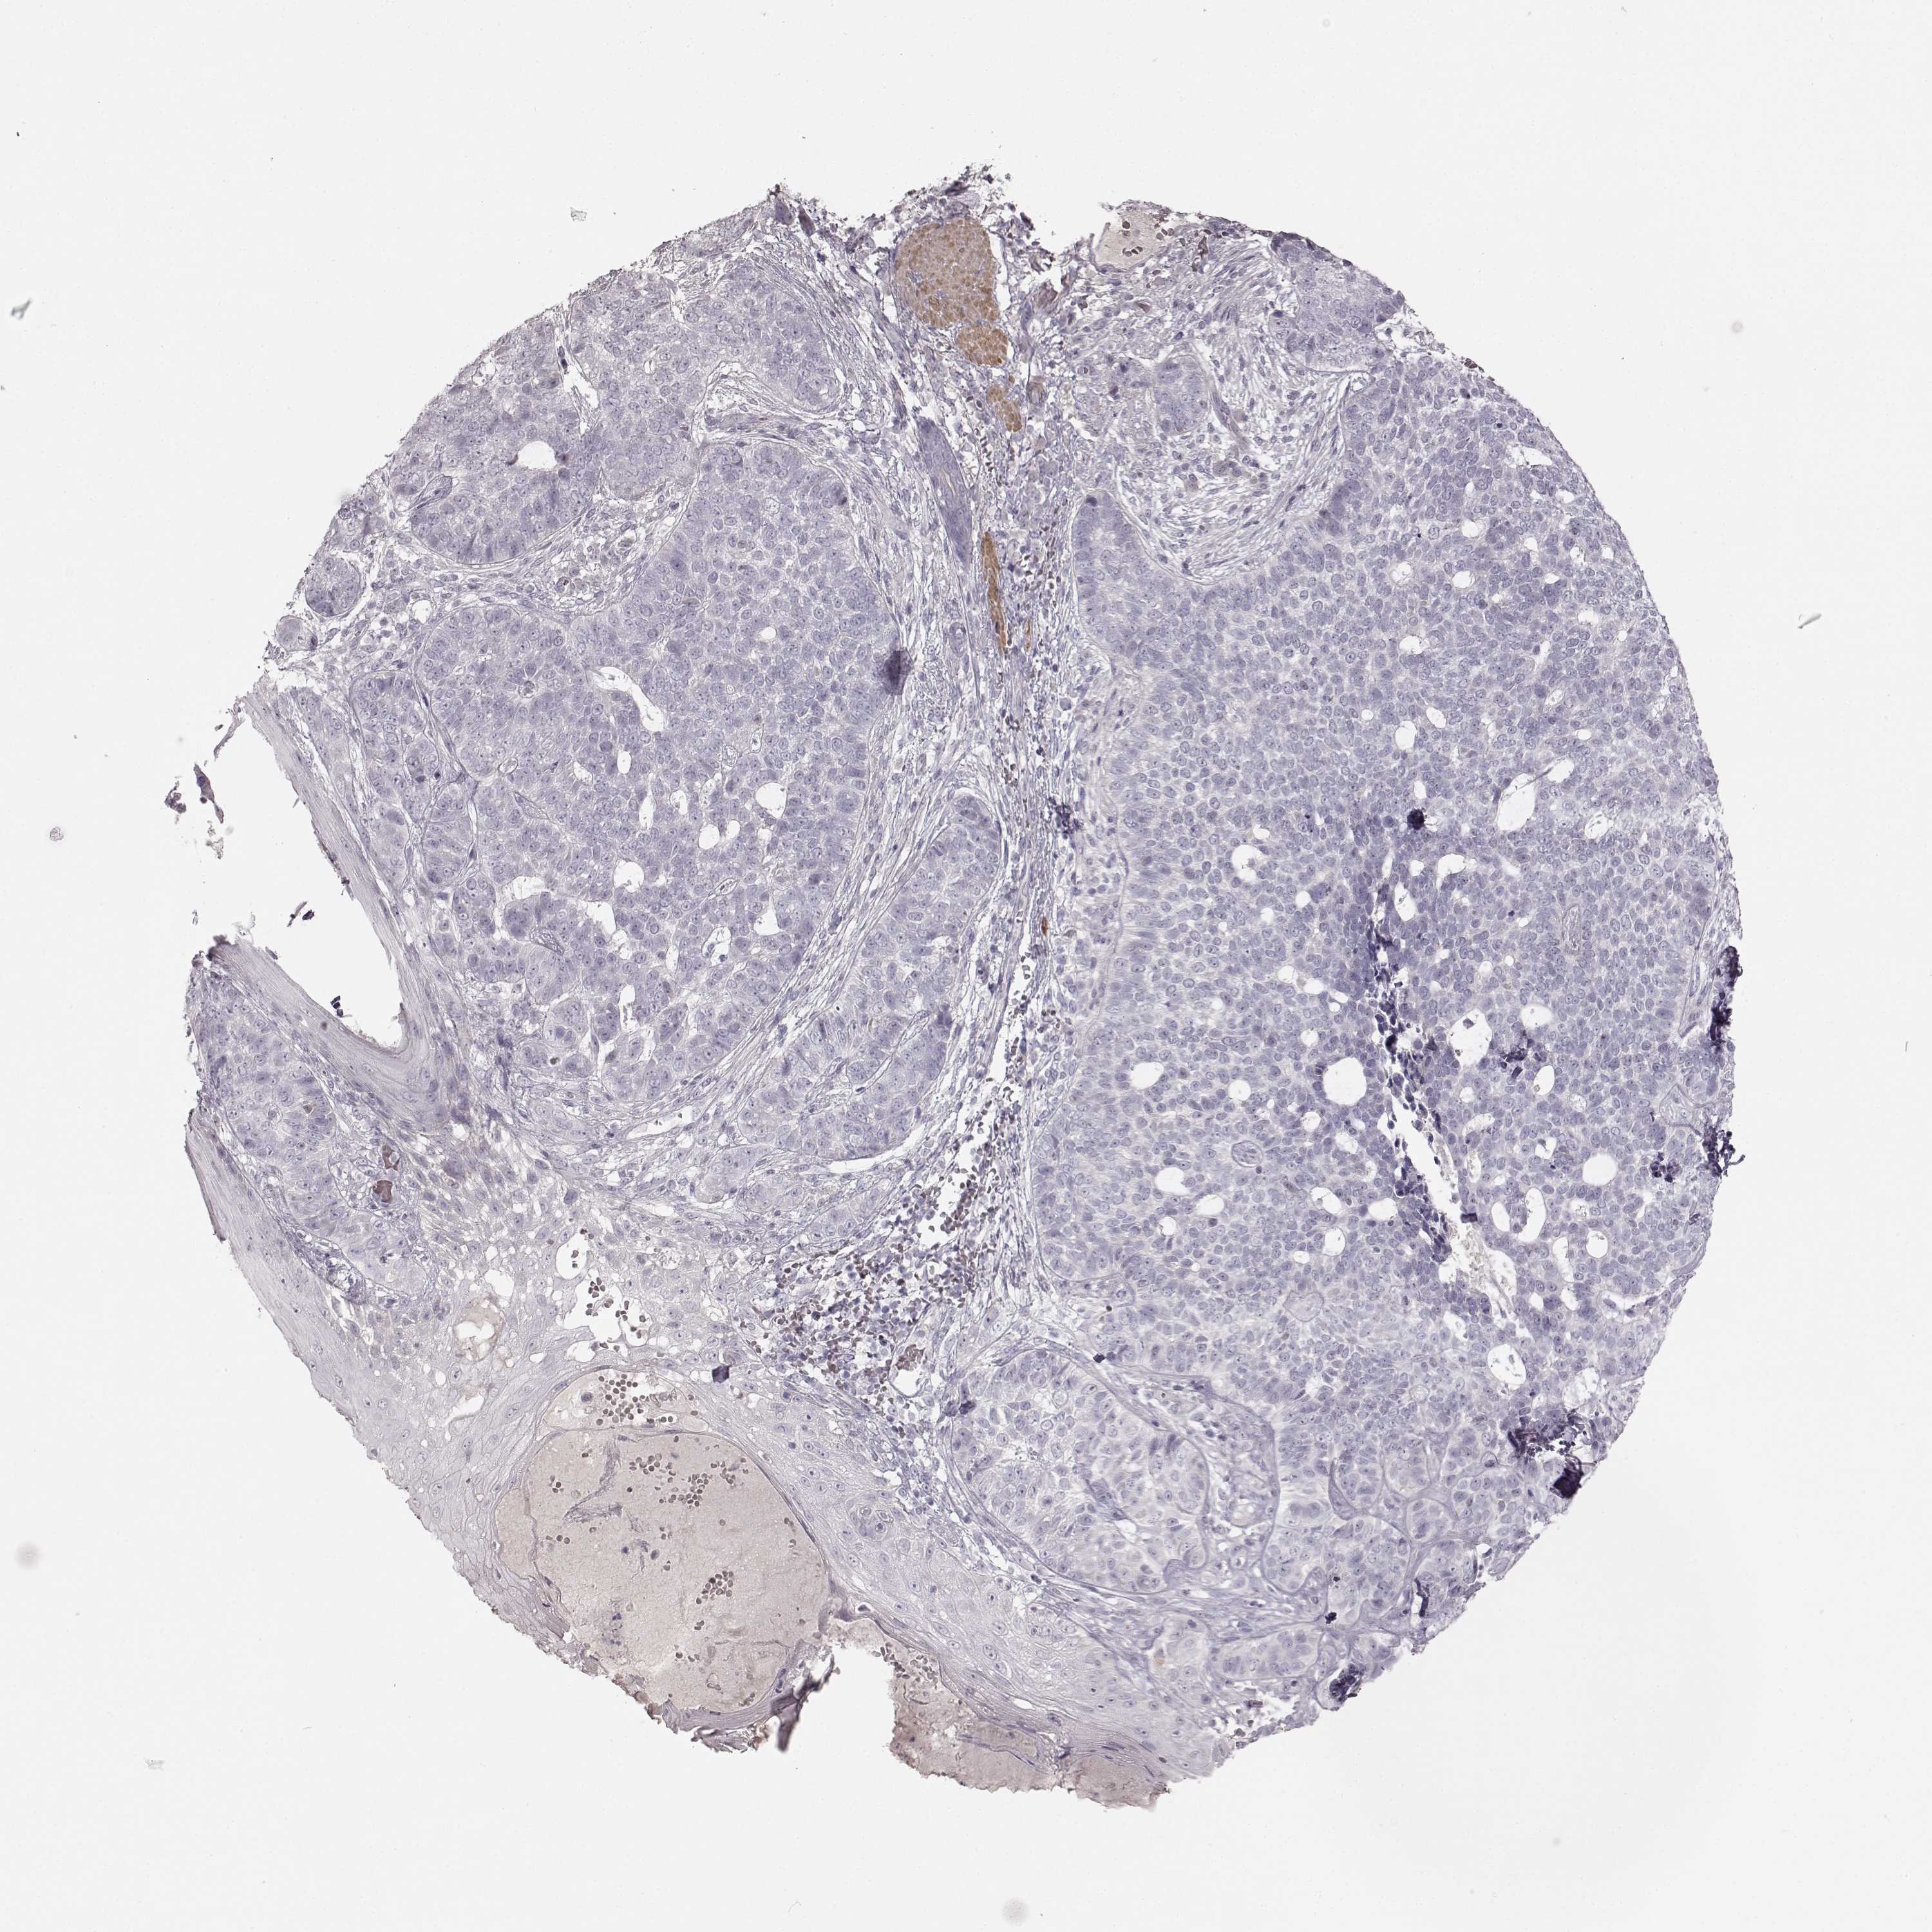

Basal cell and squamous cell cancer

SKIN CANCER - Protein expressioni

A mouse-over function shows sample information and annotation data. Click on an image to view it in a full screen mode. Samples can be filtered based on level of antibody staining by selecting one or several of the following categories: high, medium, low and not detected. The assay and annotation is described here.

Antibody stainingi

Antibody staining in the annotated cell types in the current human tissue is reported as not detected, low, medium, or high, based on conventional immunohistochemistry profiling in selected tissues. This score is based on the combination of the staining intensity and fraction of stained cells.

Each image is clickable and will lead to virtual microscopy that enables deeper exploration of all samples and also displays staining intensity scores, fraction scores and subcellular localization as well as patient and tissue information for each sample.

Antibody HPA039361

Basal cell carcinoma

Squamous cell carcinoma, NOS